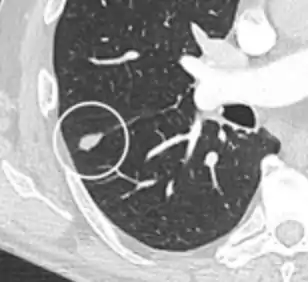

- Margin morphology: a spiculated margin is a risk factor for cancer.[8] Benign causes tend to have a well defined border, whereas lobulated lesions or those with an irregular margin extending into the neighbouring tissue tend to be malignant.[10] In particular, spiculations are highly predictive of malignancy with a positive predictive value up to 90%.[9] Also, a "notch sign", which is an abrupt indentation of the nodule, increases the risk of cancer, but may also be found in granulomatous diseases.[9]

A "notch sign".[9]

A triangular perifissural node can be diagnosed as a benign lymph node.[9]